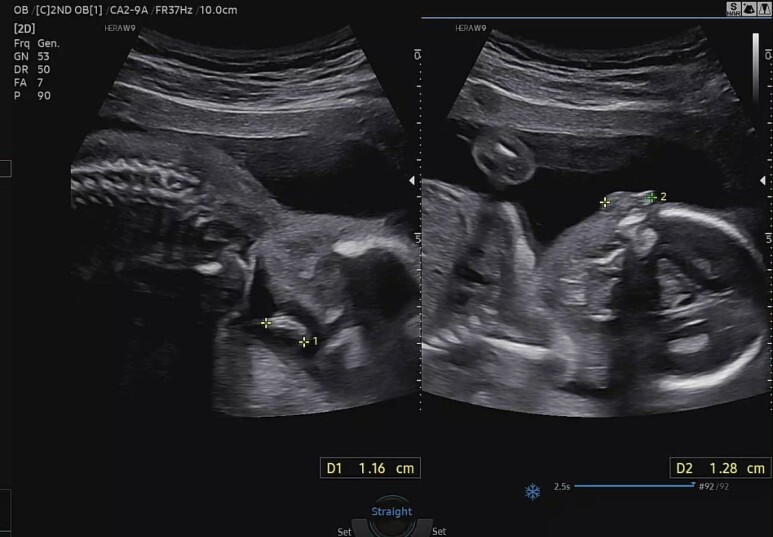

먼저 꿀잠이 머리둘레(BPD)와 직경(HC)

소뇌(CEREB)와 대실(CM)의 크기.

양수량 측정

양수 충분해서 아기 잘 놀 수 있다고 하셨다. 예에~